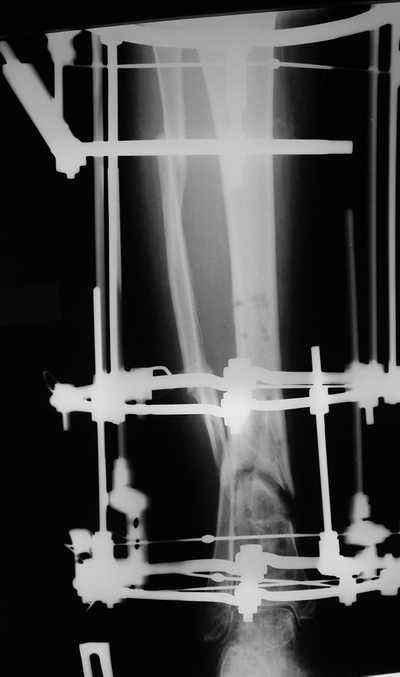

Male 54 years old, diabetic, blind in both eyes, with infected (MRSA) non union distal tibia after fracture 8 month ago. In acute phase treated by ORIF with LCP tibia and fibula. Treatment complicated by infection and after 6 month hardware was removed and treatment continued by cast fixation. You can see malposition of fragments In this stage beginning treated by Ilizarov fixation with use Hexapod system, allows anatomical position of fragments and you see signs of union.

Sorry, I wiil tray now pictures of my case.